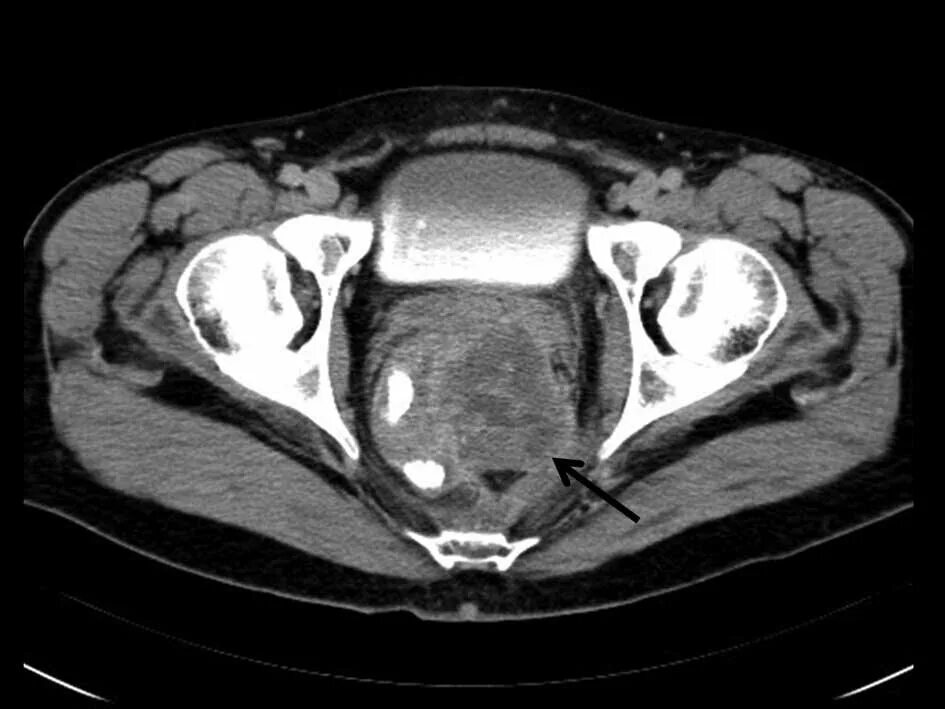

Перед мрт простаты